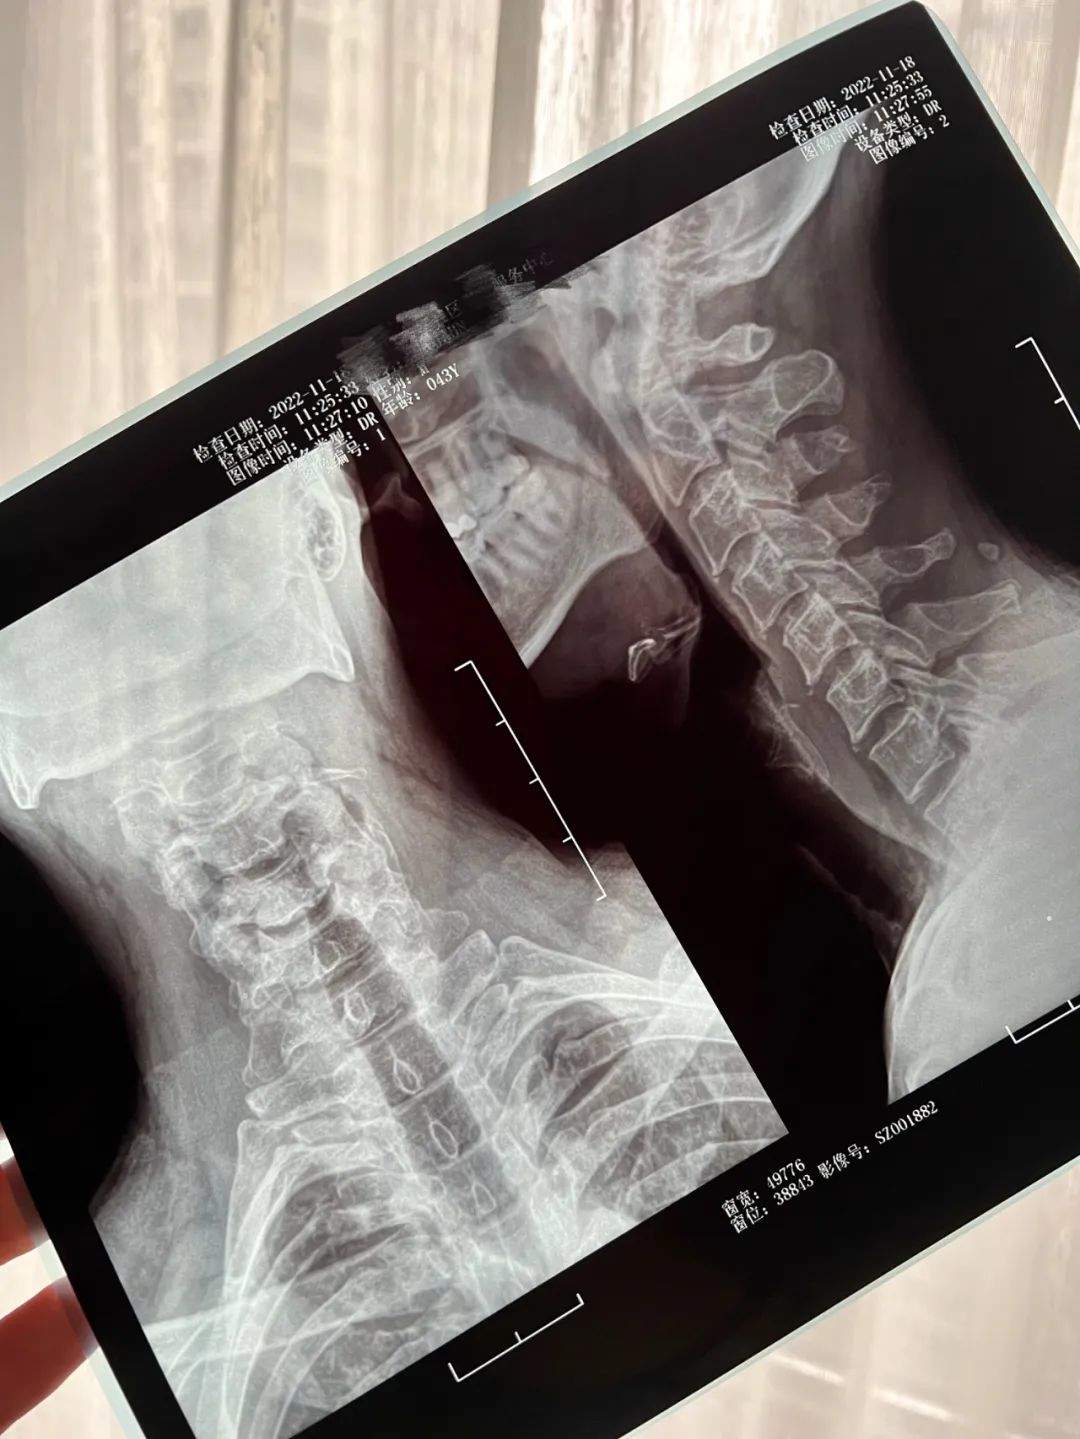

去年木馬爸爸因為頸椎問題去社區醫院拍片,也是十分高效,當場就拿到了結果